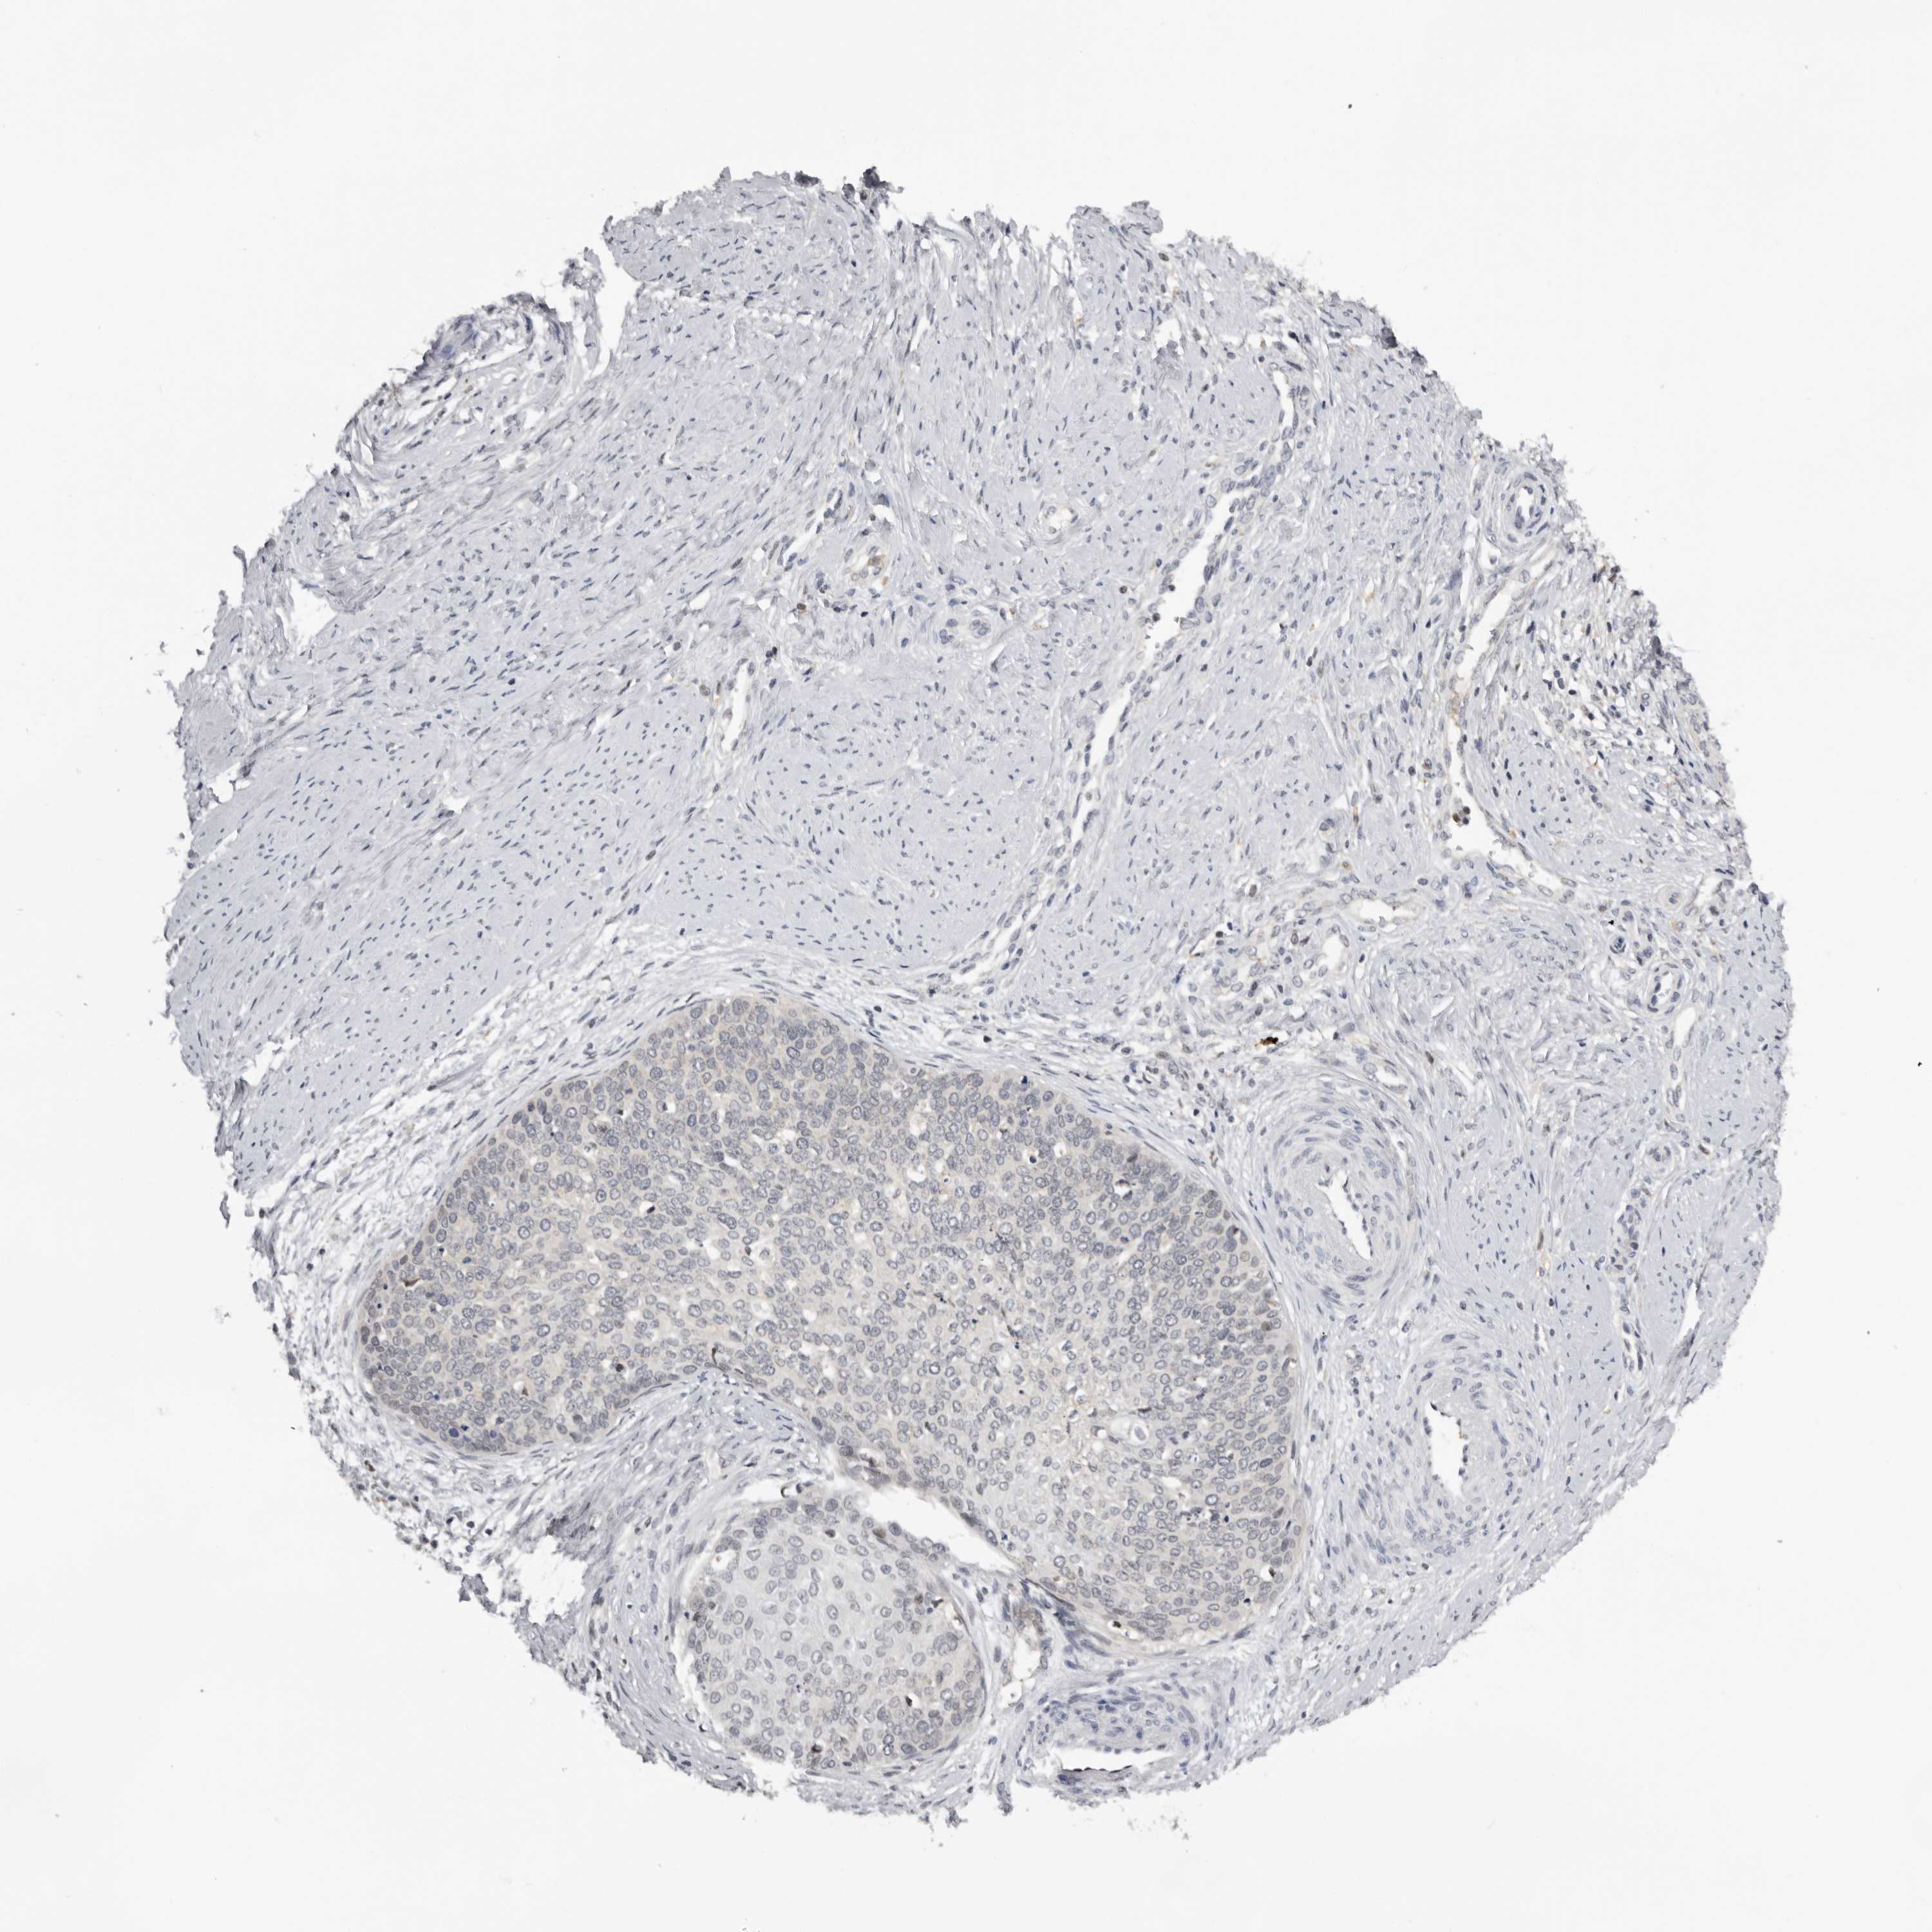

CERVICAL CANCER - Protein expressioni

A mouse-over function shows sample information and annotation data. Click on an image to view it in a full screen mode. Samples can be filtered based on level of antibody staining by selecting one or several of the following categories: high, medium, low and not detected. The assay and annotation is described here.

Note that samples used for immunohistochemistry by the Human Protein Atlas do not correspond to samples in the TCGA dataset.

Antibody stainingi

Antibody staining in the annotated cell types in the current human tissue is reported as not detected, low, medium, or high, based on conventional immunohistochemistry profiling in selected tissues. This score is based on the combination of the staining intensity and fraction of stained cells.

Each image is clickable and will lead to virtual microscopy that enables deeper exploration of all samples and also displays staining intensity scores, fraction scores and subcellular localization as well as patient and tissue information for each sample.

Antibody HPA023081

Antibody HPA023103

Antibody HPA024795

Squamous cell carcinoma, NOS

Adenocarcinoma, NOS